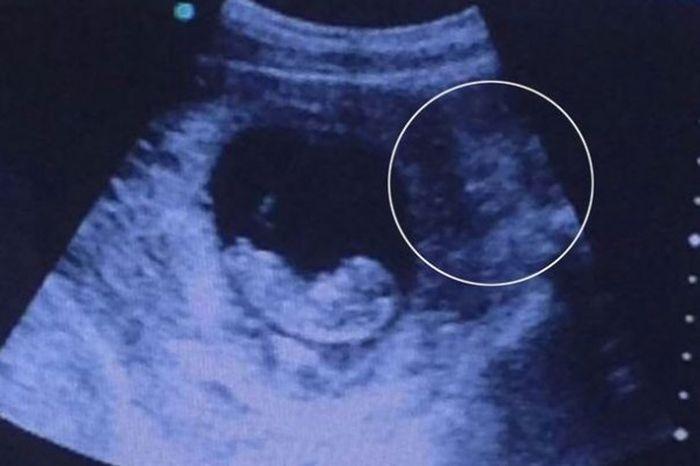

Ecografia care i-a CUTREMURAT pe toţi! Cine veghează asupra copilului nenăscut

La prima vedere, pare doar o ecografie obişnuită a unui copil nenăscut, care se odihneşte liniştit în pântecele mamei sale. Însă dacă te uiţi în dreapta fotografiei e posibil să descoperiţi ceva tulburător. Chipul unei femei a fost zărit de numeroşi internauţi.